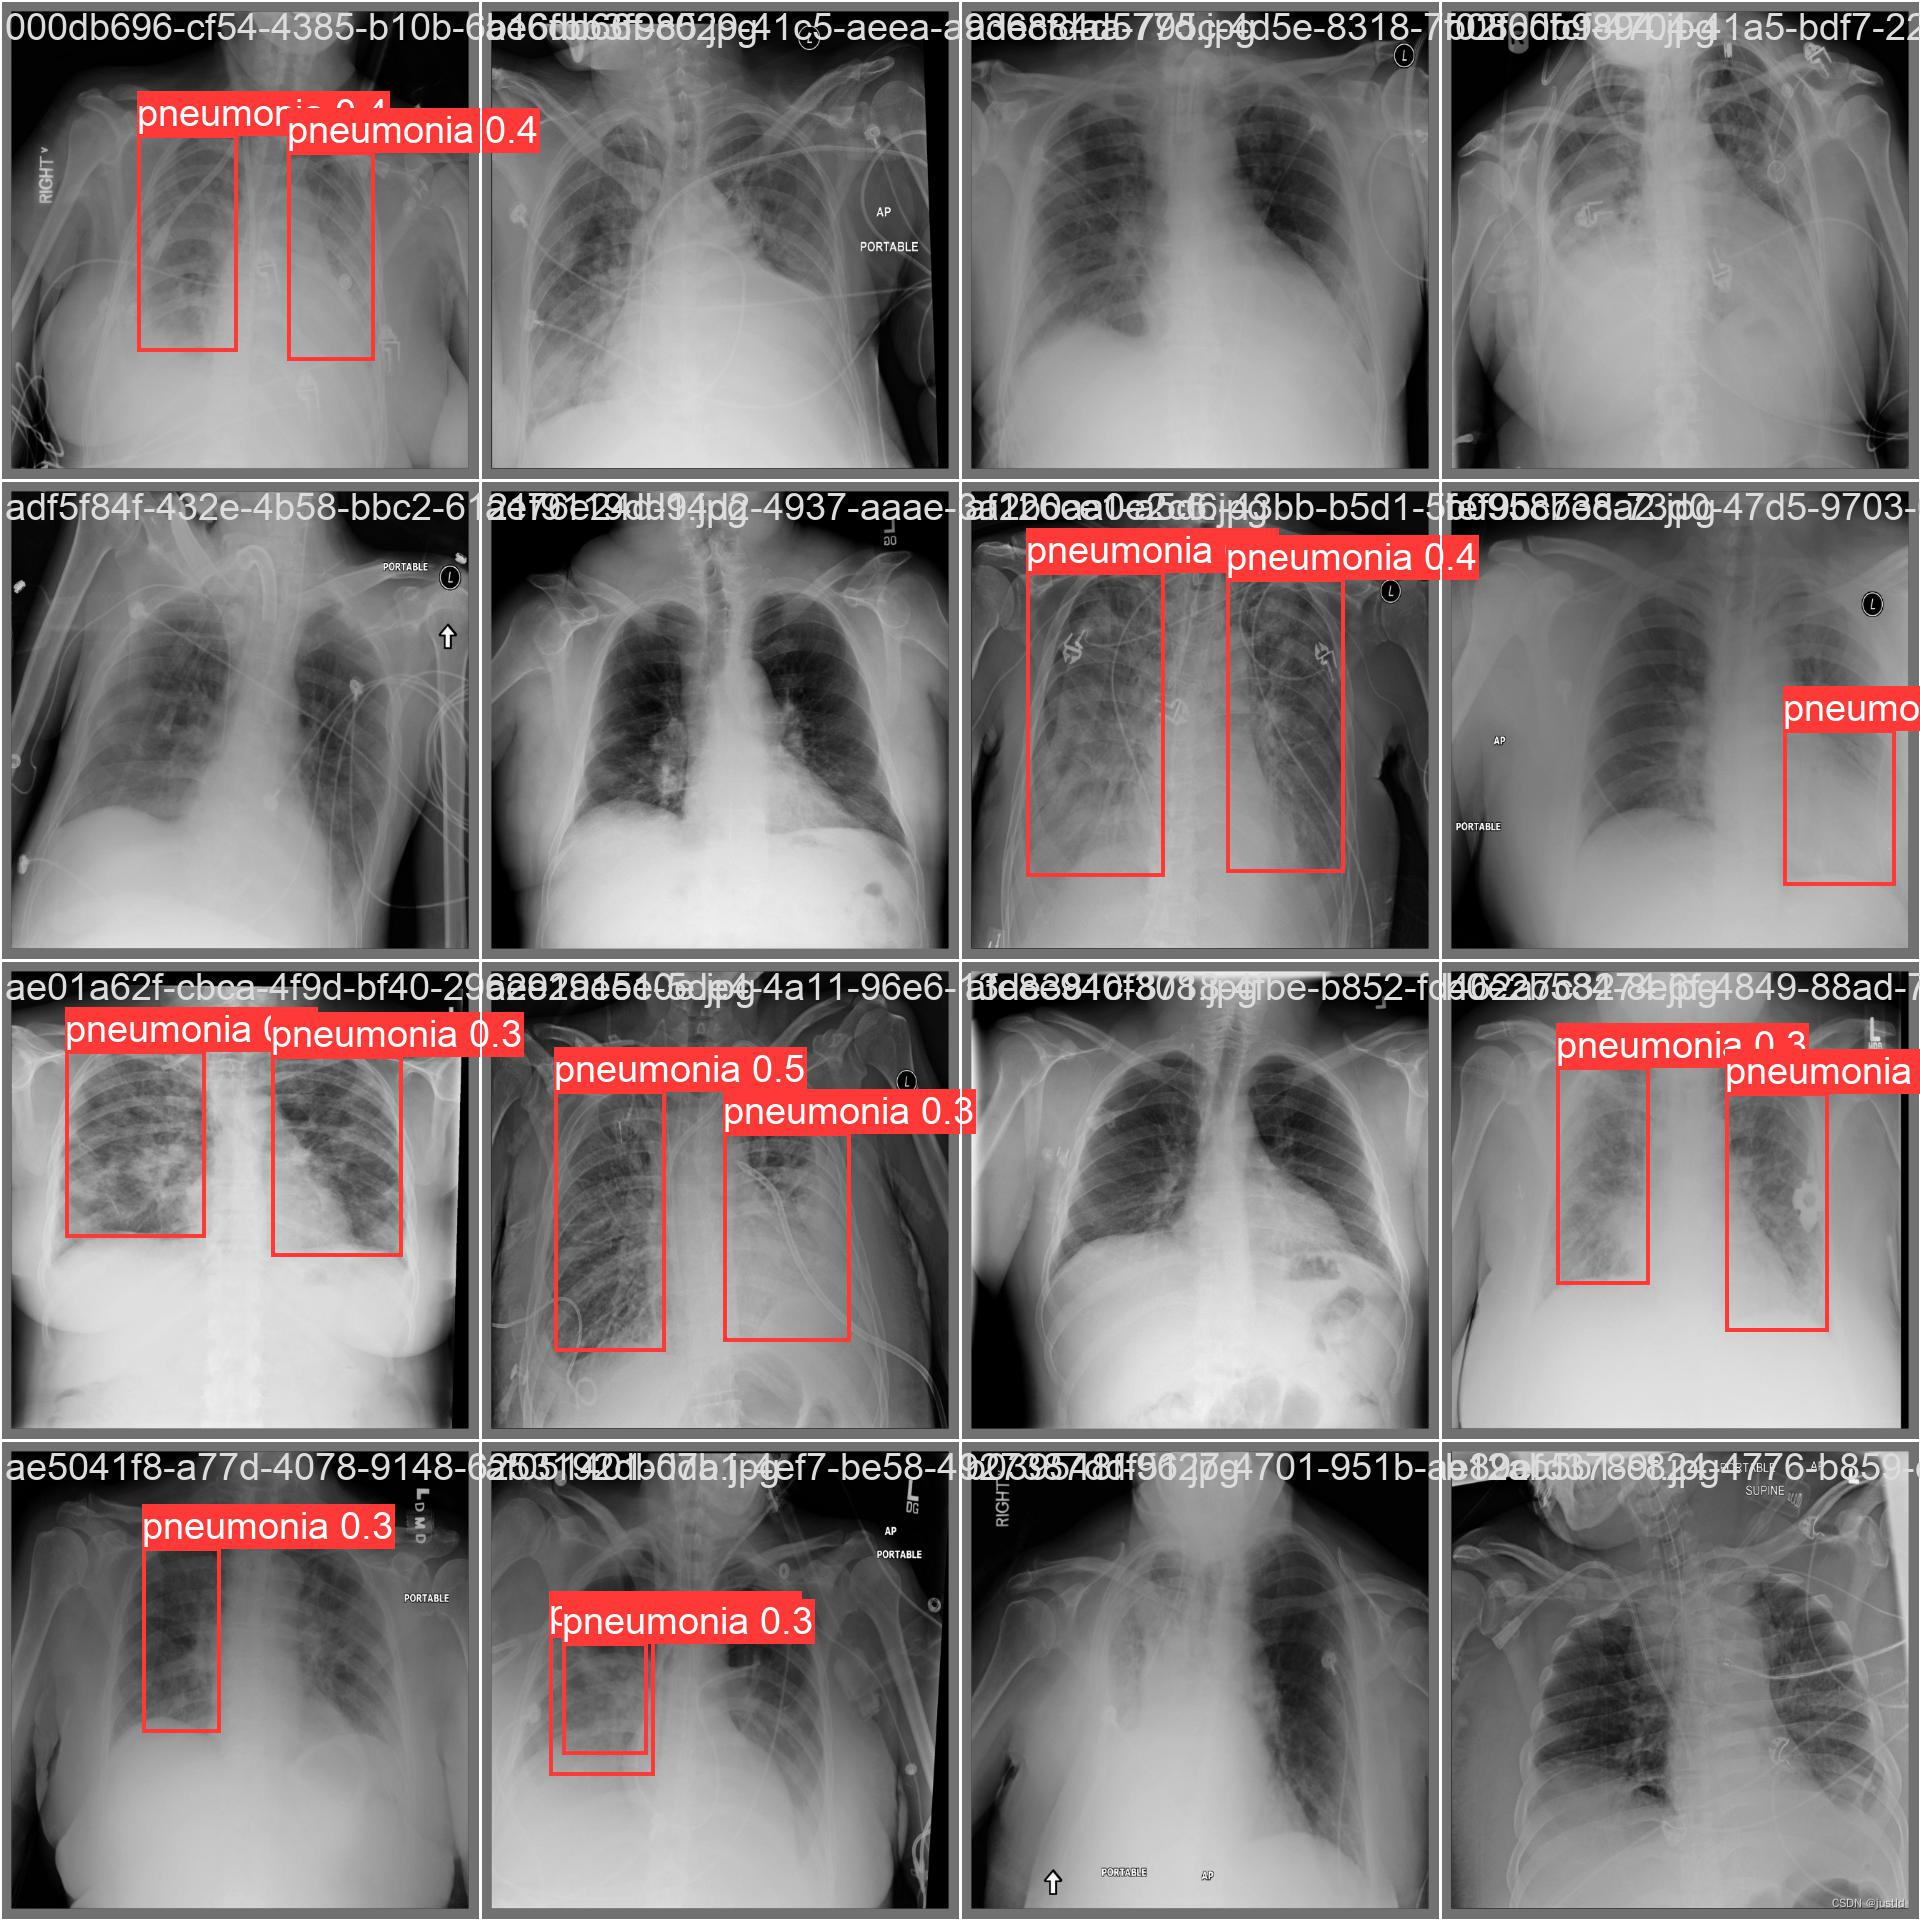

该数据集包含5950个训练数据,662个测试数据,数据如下图:

为了使用yolov8算法进行训练,需要将该数据转换为yolov8格式,本文提供转换好的数据集下载连接:RSNA Pneumonia(RSNA肺炎)yolov8格式数据集,该数据集包含5950个训练数据,662个测试数据